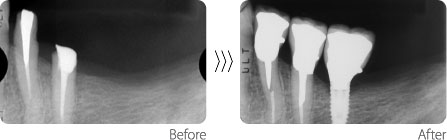

人工の歯根、インプラントが入ったレントゲン写真です。インプラント治療の際には、もとの歯があった場所に、正確にインプラントを位置させるべくCT撮影等による十分な診査診断を行っています。

画面右の矢印部分は、鼻の穴(副鼻腔)があり骨が足りない状態でしたが、骨を作る処置を行った結果、十分にインプラントが出来るだけの骨が出来ているのがわかります。